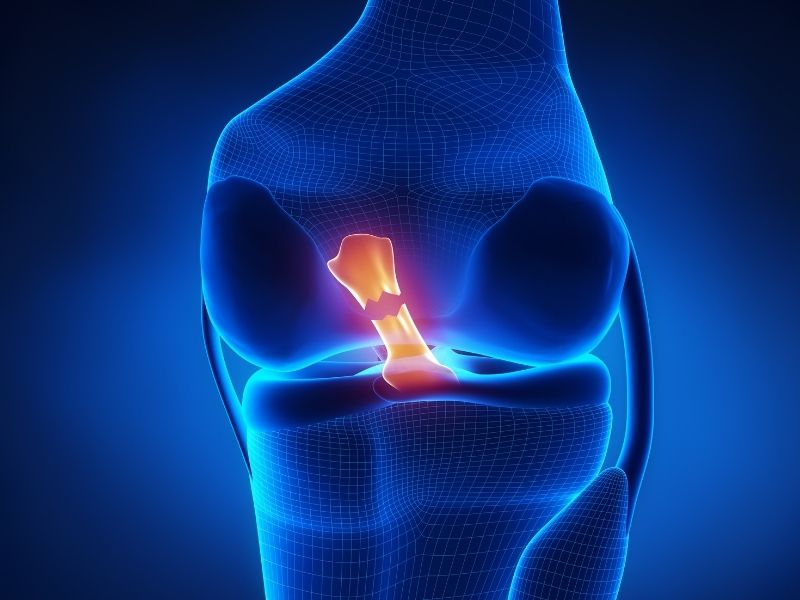

Diz rahatsızlıkları içinde en çok görülenler menisküs, çapraz bağ yaralanmaları, kıkırdak hasarları ve kireçlenmedir.

Cerrahi tedavi kararı problemin ciddiyetine ve ameliyatsız tedavilere verilen yanıta bağlıdır. Menisküs yırtığı, çapraz bağ zedelenmesi veya ileri düzey kireçlenme durumlarında ameliyat seçeneği değerlendirilebilir.